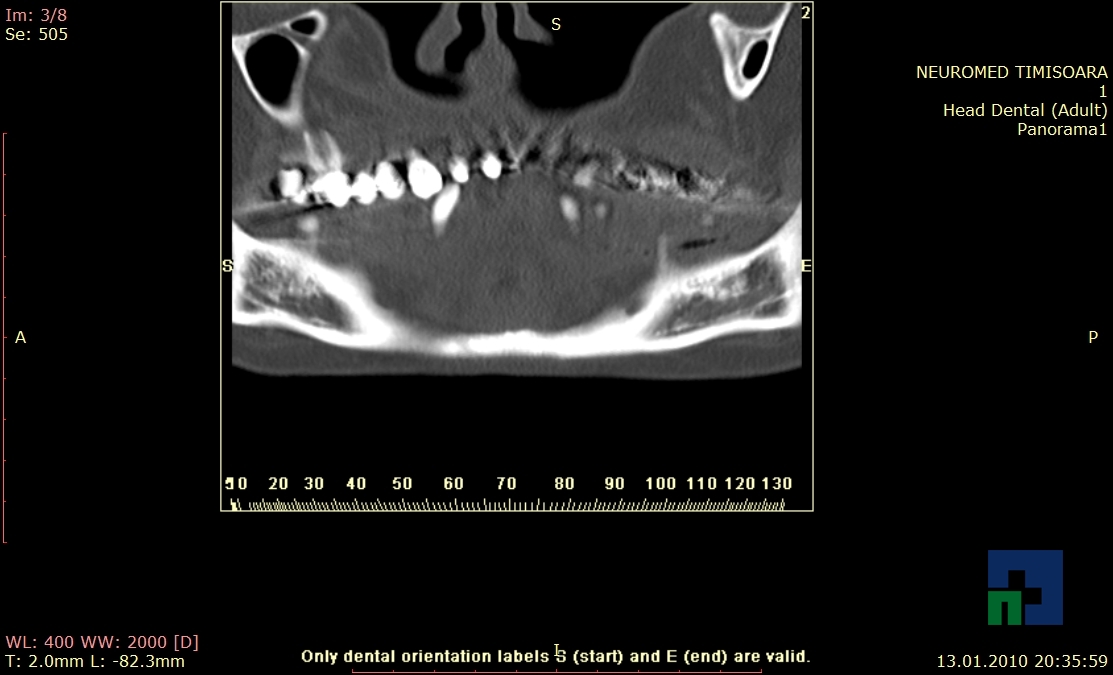

- Diagnosticul fracturilor:

- Unice

- Multiple

- Cu înfundare

- Complexe cranio-sinusale

- Complexe cranio-etmoidale

- Complexe cranio-orbitare

- Complexe cranio-faciale